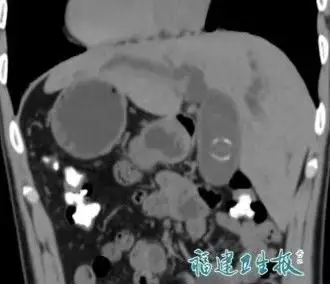

綜合內媒報導,福建發現一宗極為罕見的醫學個案。一名男子陳先生(化名)因出現腹痛及皮膚發黃等症狀求醫,經詳細檢查後被確診為「完全性內臟反位」,即俗稱的「鏡面人」。他的心臟、肝臟及脾臟等五臟六腑位置,與常人完全相反,如同照鏡子般左右顛倒,全球發生率僅約百萬分之一。

醫療團隊指出,陳先生屬於「完全性內臟反位」,除心臟位於右側(右位心)外,腹腔內器官也呈180度鏡像排列。這類患者大多器官功能正常,若無其他先天畸形,日常生活與常人無異。不過,一旦需要接受手術或急救,風險便大幅提升。

主刀醫生、肝膽外科主任李海濤表示,手術最大困難在於「所有解剖知識都要倒過來用」。腹腔鏡畫面中,肝臟在右、膽管在左,器械操作方向也須完全逆向,稍有不慎,便可能誤傷重要血管或器官。